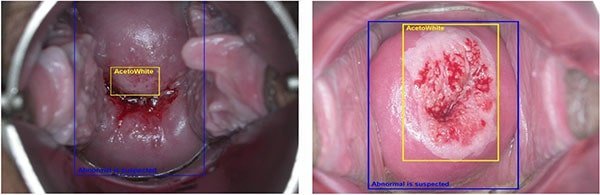

سپس یک محلول اسیدی ملایم با یک سواب پنبه ایی یا توپ پنبه ایی روی دهانه رحم و واژن شما مالیده می شود. این مایع باعث می شود که نواحی غیر طبیعی راحت تر دیده شوند. ممکن است احساس حین استفاده از این محلول احساس سوزش خفیفی داشته باشید.

نتایج غیر طبیعی در کولپوسکوپی شامل موارد زیر است که نیاز به درمان و بررسی دارند:

-دیسپلازی دهانه رحم (تغییرات پیش سرطانی در بافت دهانه رحم).

-سرطان دهانه رحم.